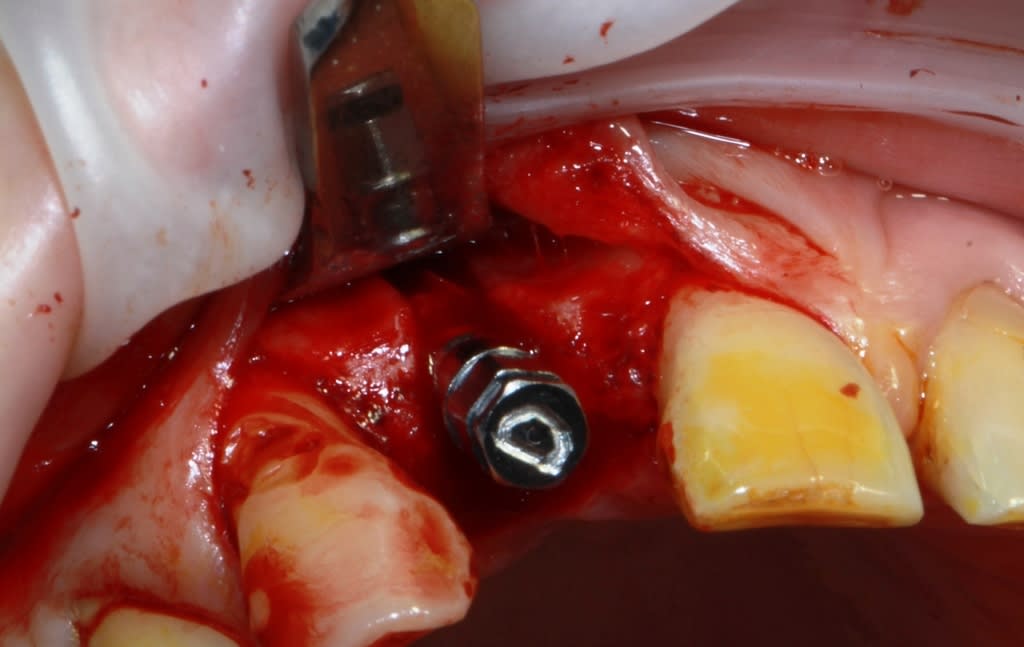

un petit cas comme j'aime, perte de 11, avec atteinte de la paroi vestibulaire.

Manipulation de la paroi palatine, afin de déplacer la moitié de l'os en vestibulaire, et pose d'un Px (Anthogyr) utilisation, de lame 11, ostéotome demi lune de Tatum, spreader (Meissinger) et divers.

Le plus bluffant quand tu fais défiler les photos c’est que tu passes de la dernière (avec l’implant en place) à la 1ere avec la fenestration!

afin d'éviter la "casse", il faut un os assez souple et prendre son temps.

Le volet n'est pas vraiment "déplacé", il reste solidaire en apical, il est donc "manipulé".

Il est important bien sûr qu'il n'y ai pas de pression dessus ensuite, donc provisoire collé ou rien.